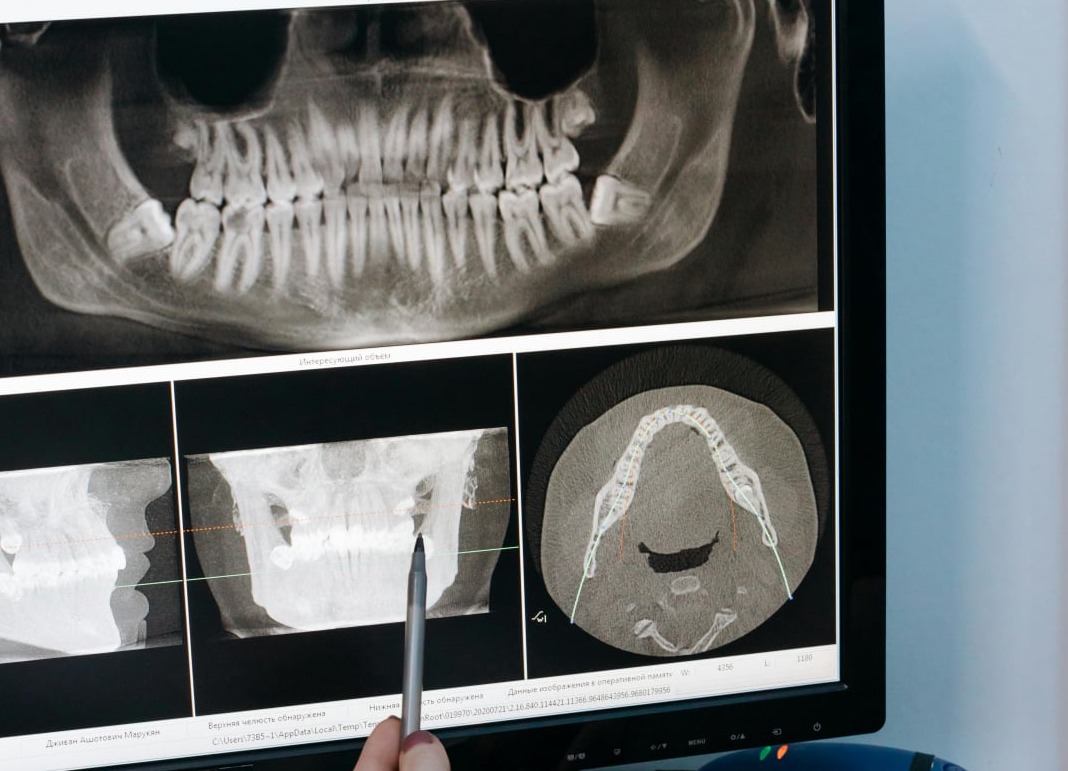

CBCT technology (3D/Cone Beam)

Cone-beam computed tomography (CBCT) was developed and introduced specifically for dento-maxillofacial imaging. It possesses a number of advantages such as lower effective radiation doses, lower costs, fewer space requirements, easier image acquisition, and interactive display modes.

• High-Resolution Imaging

• Lower Radiation Exposure

• Faster and Comprehensive Scans